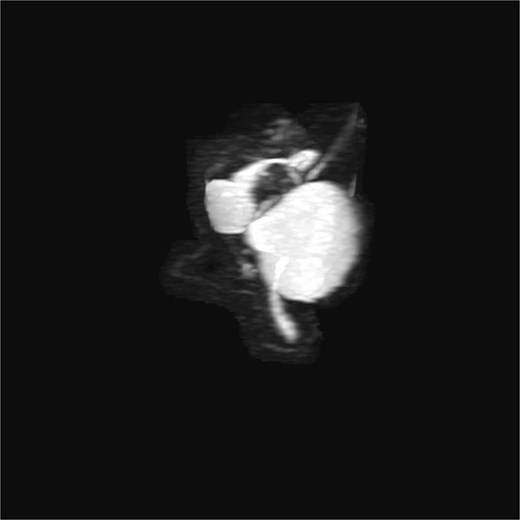

3D T2-weighted MRCP with maximum intensity projection (MIP), showing duplicated gallbladder (H-type) and biliary anatomy.

Most cases are diagnosed incidentally, but preoperative identification via MRCP is crucial in complex or recurrent biliary disease [8] (Figs 2–5). Anatomical variants increase the risk of bile duct injury, bleeding, or incomplete surgery [9]. Surgically, duplicated gallbladders pose technical challenges, especially when inflamed or fibrotic. Higher conversion and complication rates have been reported [7, 11].